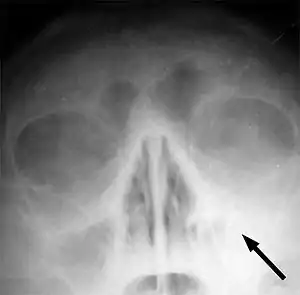

| سینوزیت در کاوک چپ فک بالایی. به علت کمبود هوا در حفره چپ و وجود ترشحات، این ناحیه سفید دیده میشود. | |